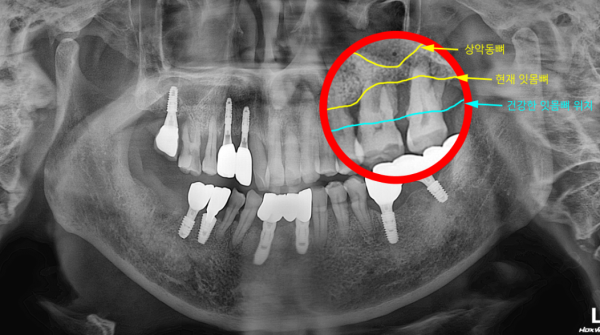

2) 진단 포인트: 왜 일반적인 임플란트가 어려웠나

파노라마 및 임상 소견에서 확인한 핵심은 다음과 같습니다.

#26, #27 부위 중증 치조골 흡수 진행

상악동이 하방으로 위치하여 임플란트 길이/안전거리 확보가 제한

치아를 보존하더라도 예후가 불리한 상태

즉, “발치하고 바로 임플란트만 심는 방식”으로는 안정적인 기반을 만들기 어려웠고, 뼈 조건을 회복시키는 술식이 함께 필요한 상황이었습니다.

5) 수술 후 영상 평가

수술 직후 파노라마에서 확인한 내용은 다음과 같습니다.

* 상악동 거상된 공간의 형태가 비교적 안정적으로 유지됨

* 골이식재의 분포가 한쪽으로 치우치지 않도록 관리됨

* 임플란트 위치와 방향이 계획 범위에서 확인됨

현재는 치유 과정을 거치며 추적 관찰 중이며, 일정 기간 후 2차 수술 및 보철 단계로 넘어갈 예정입니다.